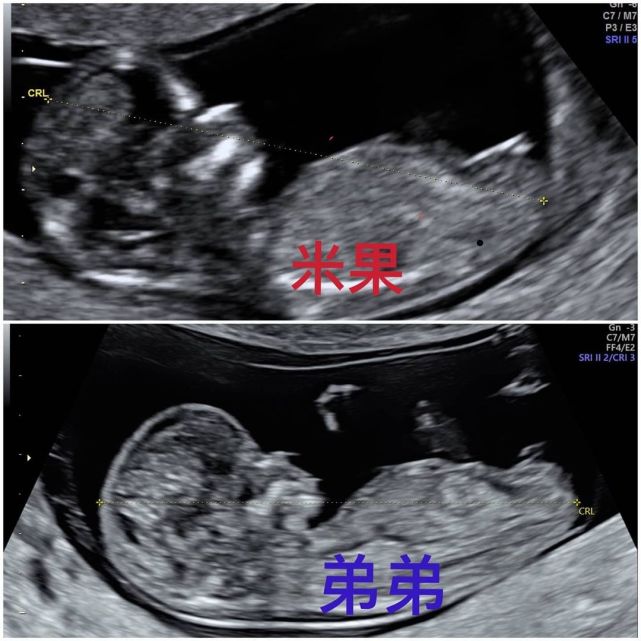

今年7月份 , 小霜再次分享了B超照 , 宣布之前冷冻的最后一颗胚胎成功着床 , 还是儿子 。 小霜透露 , 之前她一直以为自己中奖机会很低 , 没想到一次就成功了 , 而且除了前三个月打针很痛之外 , 孕期没有任何不舒服 , 也没有变丑 。